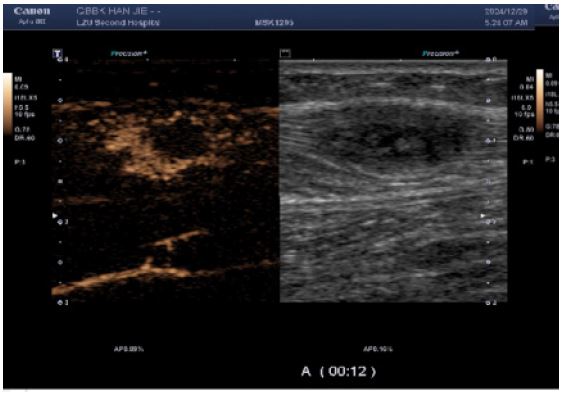

CEUS (performed next day): Demonstrated multiple hypoechoic foci in the left calf muscle layer. At 12 seconds post-contrast injection, lesions exhibited heterogeneous hyper-enhancement (> adjacent muscle tissue) with irregular non-enhancing areas.

CEUS conclusion: Enhancement pattern suggestive of benign lesions; core needle biopsy advisable.

Figure 3: CEUS suggested heterogeneous hyper-enhancement at 12 s of contrast injection.

Images are Not Display Check it